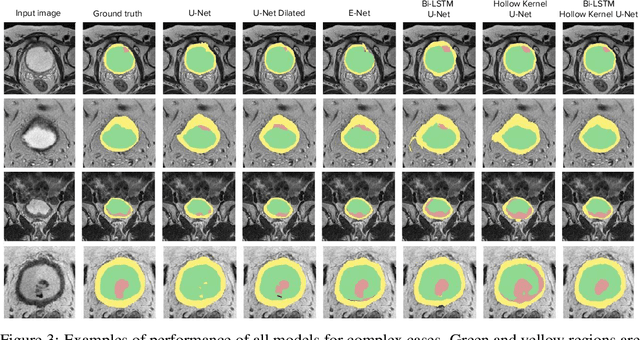

Abstract:Segmentation of certain hollow organs, such as the bladder, is especially hard to automate due to their complex geometry, vague intensity gradients in the soft tissues, and a tedious manual process of the data annotation routine. Yet, accurate localization of the walls and the cancer regions in the radiologic images of such organs is an essential step in oncology. To address this issue, we propose a new class of hollow kernels that learn to 'mimic' the contours of the segmented organ, effectively replicating its shape and structural complexity. We train a series of the U-Net-like neural networks using the proposed kernels and demonstrate the superiority of the idea in various spatio-temporal convolution scenarios. Specifically, the dilated hollow-kernel architecture outperforms state-of-the-art spatial segmentation models, whereas the addition of temporal blocks with, e.g., Bi-LSTM, establishes a new multi-class baseline for the bladder segmentation challenge. Our spatio-temporal model based on the hollow kernels reaches the mean dice scores of 0.936, 0.736, and 0.712 for the bladder's inner wall, the outer wall, and the tumor regions, respectively. The results pave the way towards other domain-specific deep learning applications where the shape of the segmented object could be used to form a proper convolution kernel for boosting the segmentation outcome.